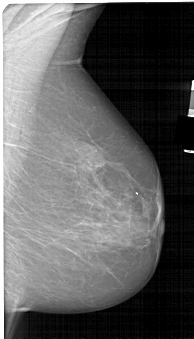

A_1565_1.LEFT_MLO

LEFT_MLO LINES 5491 PIXELS_PER_LINE 3511 BITS_PER_PIXEL 12 RESOLUTION 43.5 OVERLAY

FILE: A_1565_1.LEFT_MLO.OVERLAY

TOTAL_ABNORMALITIES 1

ABNORMALITY 1

LESION_TYPE CALCIFICATION TYPE AMORPHOUS DISTRIBUTION CLUSTERED

ASSESSMENT 4

SUBTLETY 3

PATHOLOGY BENIGN

TOTAL_OUTLINES 1

BOUNDARY